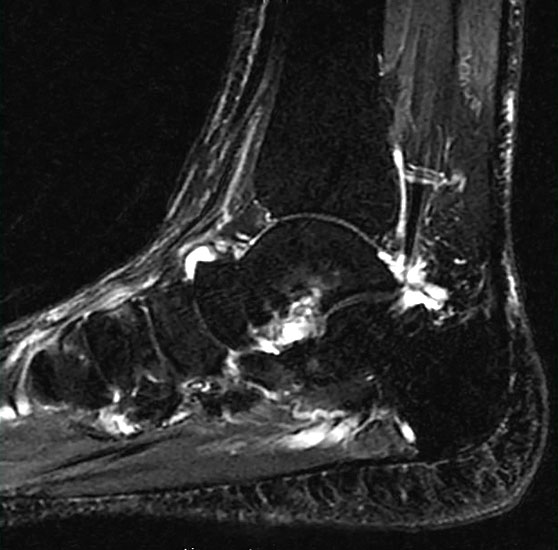

Diagnostische Methode der Wahl ist das MRT, das eine sichere Diagnosestellung erlaubt. Dabei kommt es  im betroffenen Knochen zur signalarmen Darstellung in der T1-Wichtung während T2 gewichtete Darstellungen als Folge des Ödems mit einer  Signalanreicherung in den betroffenen Skelettabschnitten und oft auch in den benachbarten Weichteilen imponieren

10.

Mitunter kommt es im Krankheitsverlauf zur verzögerten Migration des Ödems in benachbarte Skelettabschnitte (z.B. Migration vom Talus in die distale Tibia oder in den Kalkaneus) (Abb. 2 und 3), was den Krankheitsverlauf erheblich prolongieren kann.